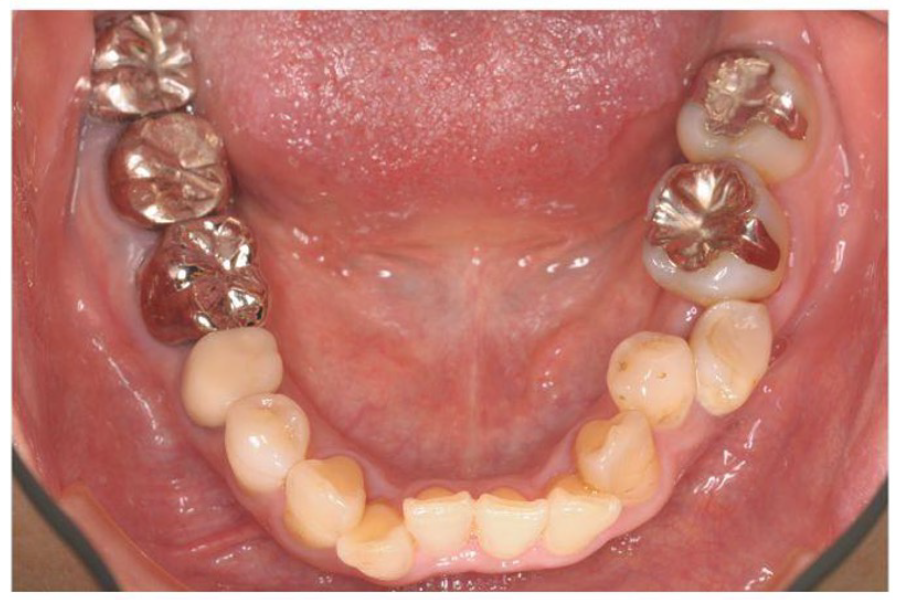

治療前